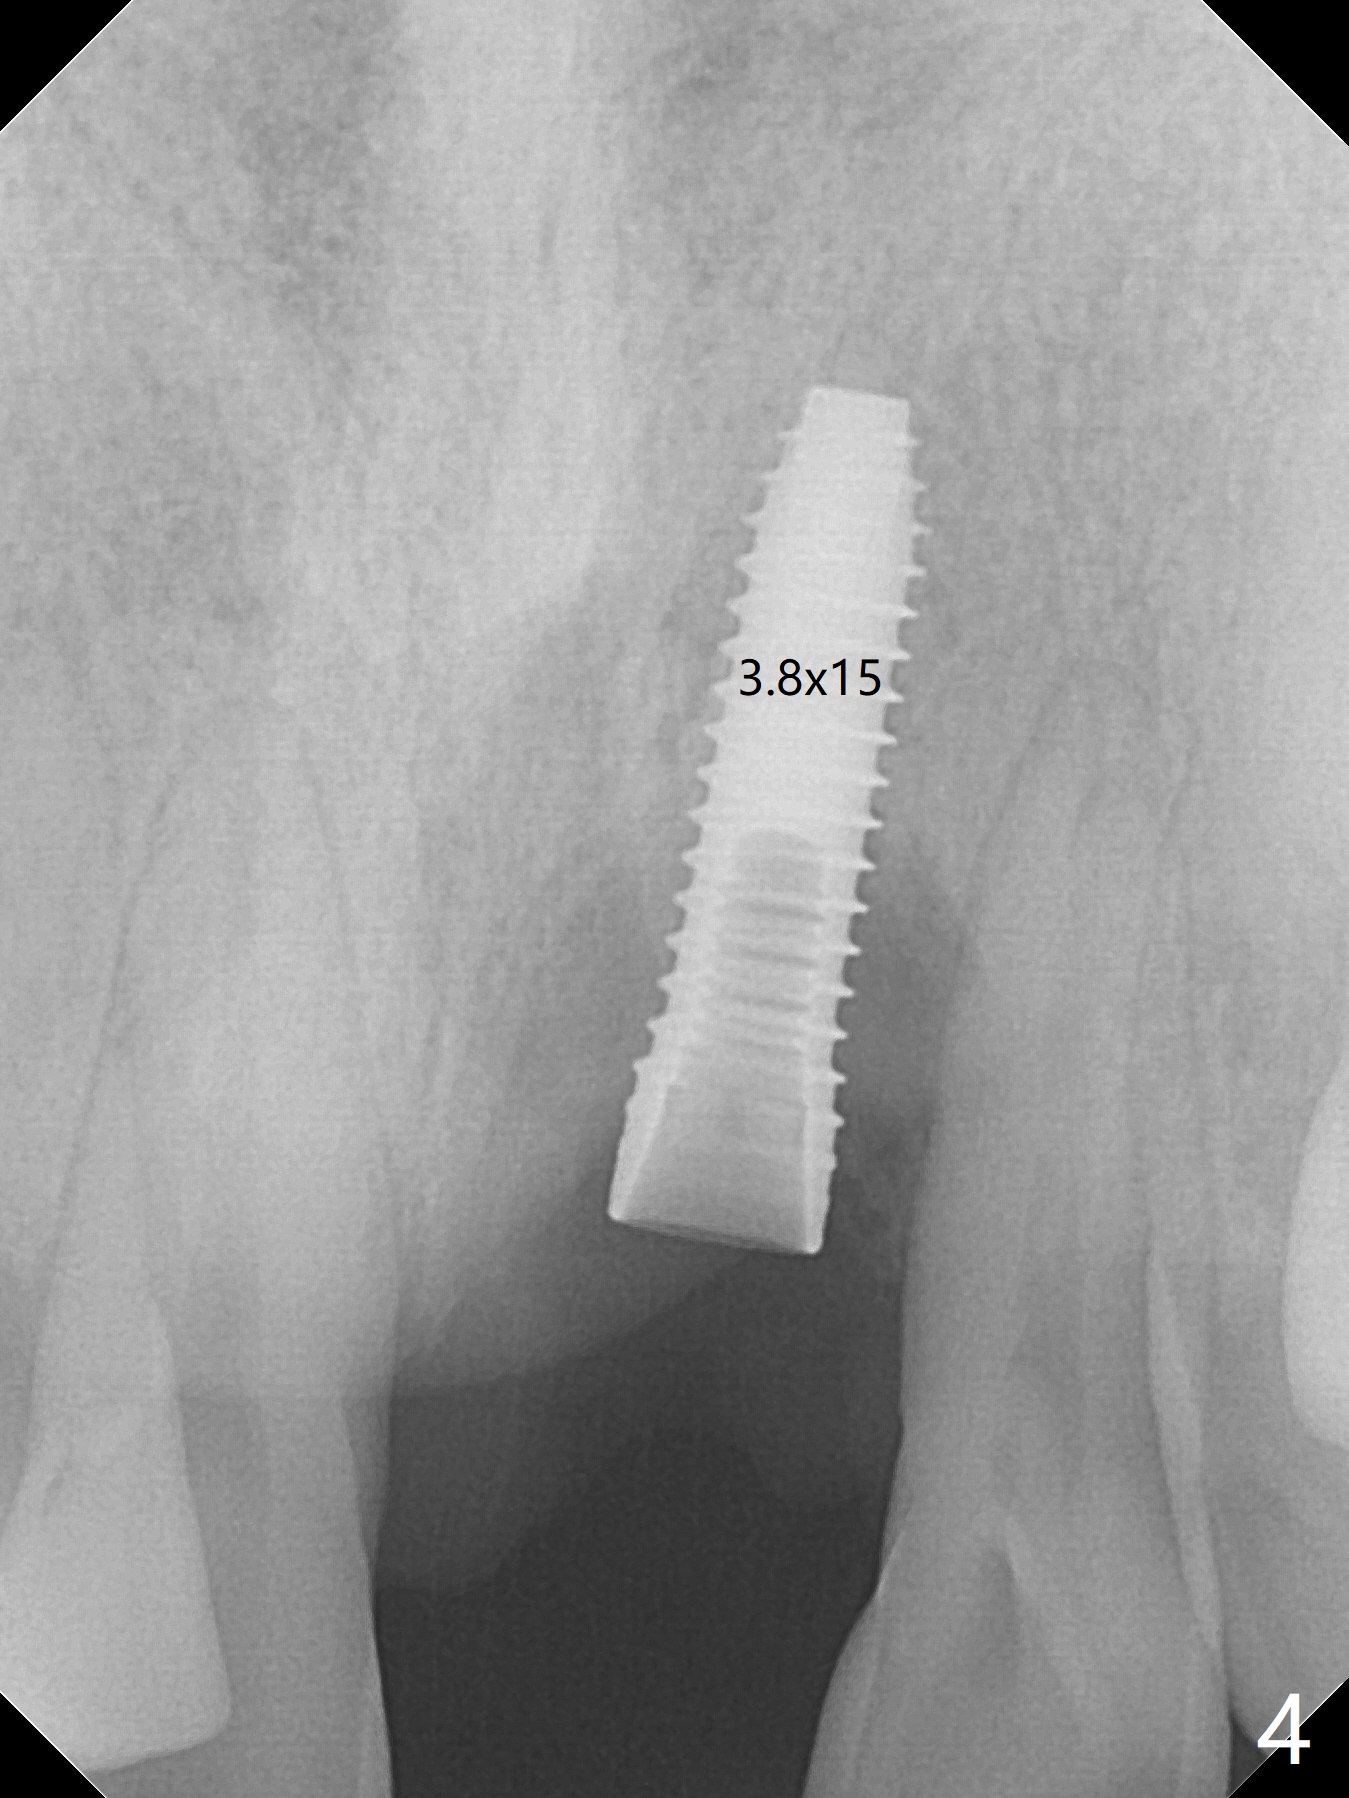

Immediately preop PA confirms loss of the buccal plate at #9 (Fig.1 *). In contrast the palatal crest is ~ 4 mm subgingival (WNL) after extraction. When initial osteotomy reaches 18 mm, there is moderate hemorrhage, probably due to close to the nasal floor (Fig.2 red dashed line). Following sequential osteotomy, a 3.8x15 mm dummy implant is placed partially (Fig.3 (pink: apical osteotomy)). After placement of an implant with the same dimension as the dummy's (Fig.4), PRF is laid against the inner surface of the buccal defect and allograft (Fig.5 *) is packed mainly in the buccal gap before and after insertion of a 4.5x5(4) mm abutment. The patient is satisfied with the immediate provisional (Fig.6: 1 week postop). The buccal margin of the provisional is shortened with exposure of bone graft to facilitate gingival downgrowth (Fig.6: 1 month postop). The buccal plate seems to collapse nearly 2 months postop (Fig.8 *), probably due to loss of the bone graft. The abutment is exposed buccally (Fig.9). The margin of the abutment is reprep and the provisional is relined so that the margin of the provisional is palatal to the buccal gingival margin. In 2-3 weeks, a temporary abutment will be used to bulk the buccal gingiva. The gingiva seems to have downgrown; the buccal plate collapse appears normal nearly 3 months postop (Fig.10). The patient is more concerned about cross bite at #7. A temporary abutment is not used. The bone graft remains in place 3.5 and 4.5 months postop (Fig.11,12 *). Between 3 and 4 months postop, the mesial surface of the abutment has been trimmed (Fig.12 >). Since the mesial surface of the tooth #10 will be reduced (white curved line) to correct the upper dental midline, an angled abutment (red line) seems to be necessary to shift the provisional distal.